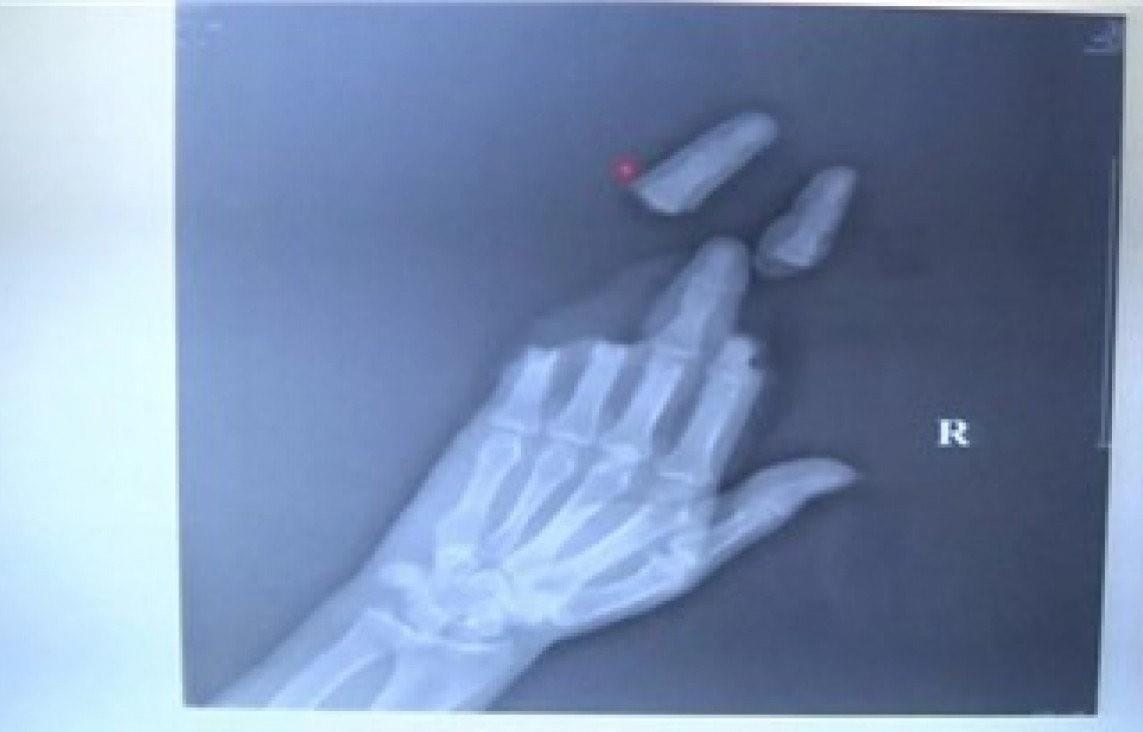

| Một người đàn ông bị sợi dây quấn chặt, làm đứt lìa ba ngón tay. Ảnh: South China Morning Post. |

Jin Degao, bác sĩ phẫu thuật, cho biết khi bệnh nhân được đưa đến đây, từ ngón trỏ đến ngón út của anh ấy đã bị cắt đứt. Mặc dù ngón giữa chưa đứt lìa, chỉ còn phần xương là nguyên vẹn. Ngoài ra, tất cả mạch máu, dây thần kinh và gân cơ đều bị cắt đứt.